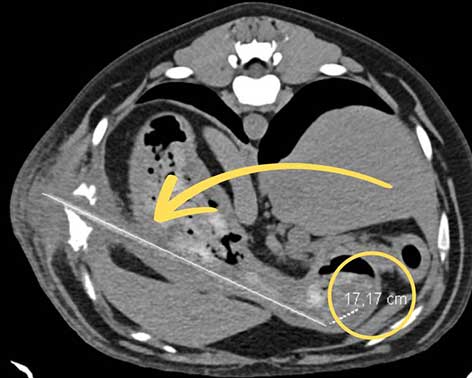

Im CT dann deutlich: Ein rund 17 Zentimeter langer Holzspieß hat sich durch die Magenwand gebohrt.

Ein anschließendes CT bestätigte den Verdacht und zeigte das Ausmaß der inneren Verletzung: Ein rund 17 Zentimeter langer Holzspieß hatte sich durch die Magenwand gebohrt und war weiter durch die Bauchwand gewandert. Besonders dramatisch: Der Fremdkörper war inzwischen vollständig eingewachsen, das umliegende Gewebe stark entzündet und verändert. An einer betroffenen Rippe zeigten sich dadurch bereits beginnende Auflösungserscheinungen.